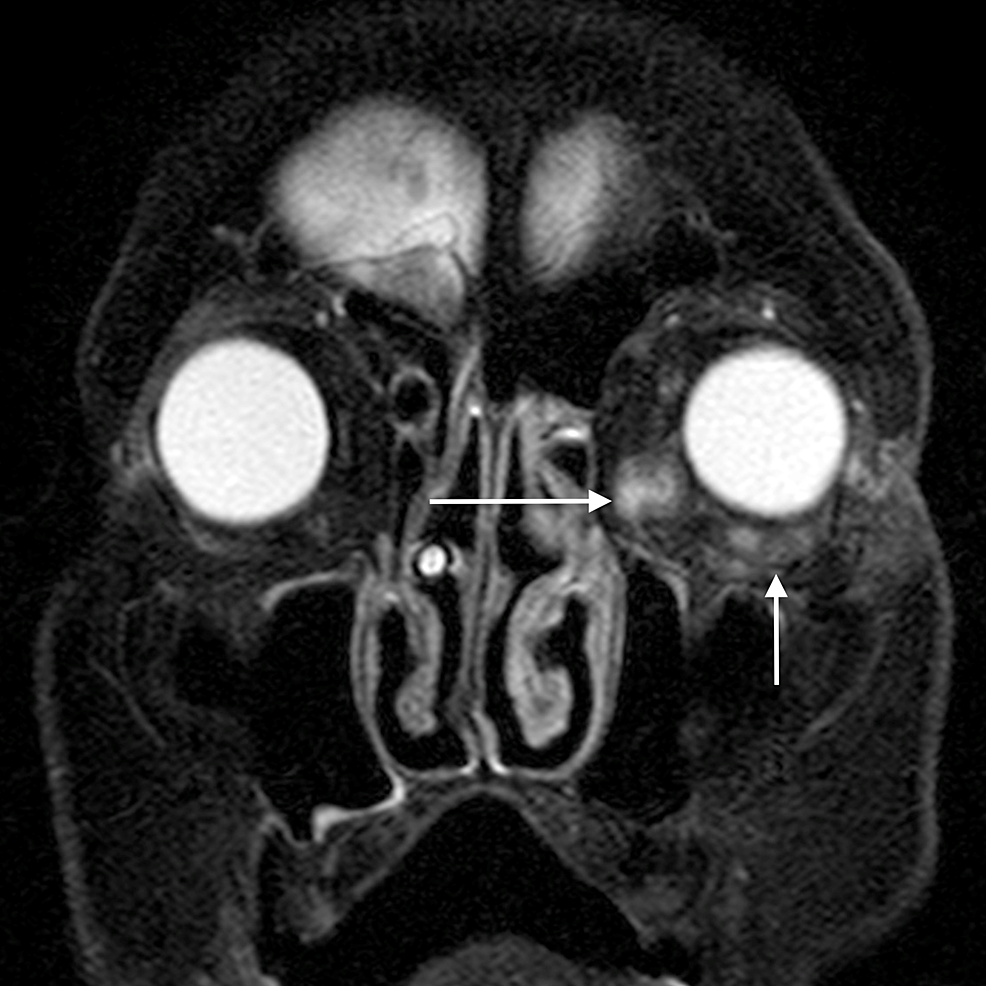

Orbital cellulitis causes diffuse, oedematous infiltration of the orbital connective tissue that is best demonstrated by the high signal intensity in T2-weighted fat-saturated sequences. Other findings are swelling and ill-defined margins of the extraocular muscles and exophthalmos [2]. Orbital cellulitis may be complicated by an abscess, which may form in the extraconal or intraconal orbit separate from the bone [3].

The main complications of orbital cellulitis (Figures 2-4) encountered in our study were:

1. An orbital abscess (Figures 5-6);

2. Preseptal cellulitis and abscess (Figures 7-8);

3. Periorbital cellulitis (Figures 9-10);

4. Dacryoadenitis (Figures 11-12);

5. Optic neuritis/perineuritis (Figure 13);

6. Cavernous sinus thrombophlebitis and thrombosis (Figure 14).

The most common complication of orbital cellulitis was orbital/periorbital abscess formation (eight cases, 53.3%), followed by optic neuritis (four cases, 26.67%), intracranial involvement (four cases, 26.67%), dacryoadenitis (three cases, 20%) and cavernous sinus thrombophlebitis (three cases, 20%).